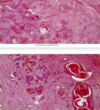

Stomach, Signet Ring Carcinoma

Invasion by MALIGNANT TUMOR composed of signet ring cells. These cells are poorly cohesive and have clear cytoplasm with dark eccentric nuclei

Malignant

Signet ring cells

Due to cytoplasmic mucin pushing nucleus to side